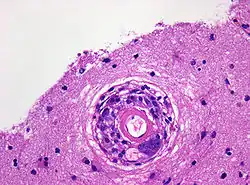

Hirnbiopsie mit Nachweis eines Blutgefäßes mit von Makrophagen und mehrkernigen Riesenzellen durchwanderter Gefäßwand. Hämatoxylin-Eosin-Färbung. Originalvergrößerung 400x

Das mittlere Alter bei Diagnosestellung beträgt etwa 67 Jahre. Die Erkrankung kann sich mit Wesensänderungen, Kopfschmerzen, Anfallsereignissen oder auch Halluzinationen bemerkbar machen. Während sich in der Kernspintomographie des Schädels lediglich unspezifische Veränderungen im Bereich des Marklagers nachweisen lassen und die Lumbalpunktion allenfalls eine moderate Erhöhung der Zellzahl ergibt, sind in der feingeweblichen Untersuchung von bei einer Biopsie gewonnenen Hirngewebsprobe granulomatöse entzündliche Veränderungen sowie Amyloidablagerungen im Bereich kleiner Blutgefäße nachweisbar. Die Lumina der Blutgefäße sind häufig thrombosiert oder weisen Zeichen einer Rekanalisation auf. Im umgebenden Hirngewebe finden sich ausgeprägte reaktive Veränderungen.